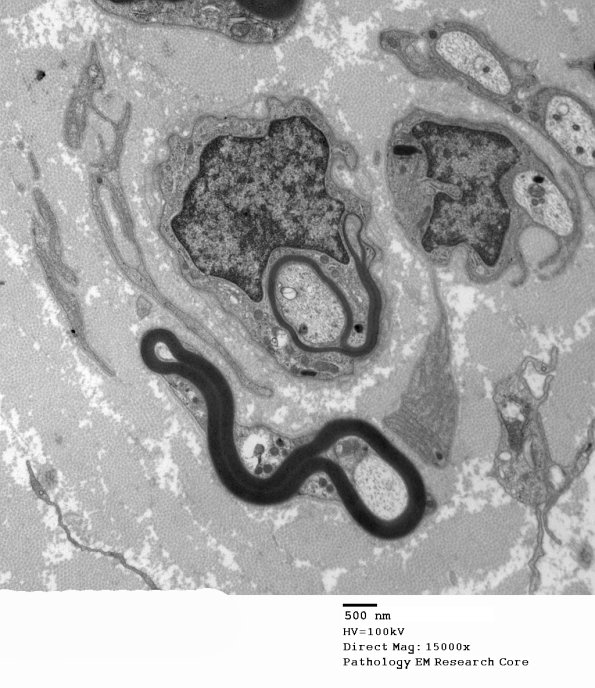

The remyelinating axon and an adjacent myelinated axon have unusual contours. (electron micrograph)